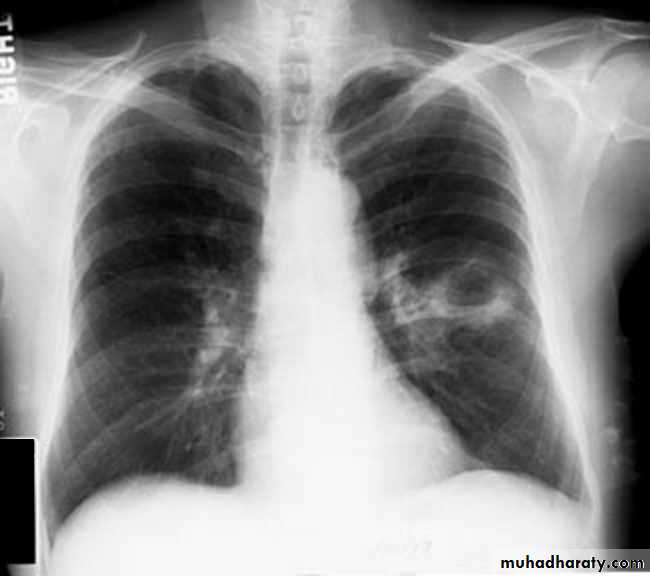

Massive pleural effusion with mediastinal shift to the left.

(A) Chest radiograph

(B) CT coronal reconstruction. A massive effusion displaces the mediastinum to the left. CT shows the important pleural effusion together with the enhanced atelectatic left lung.

Note also the depression of the right hemidiaphragm (arrows).